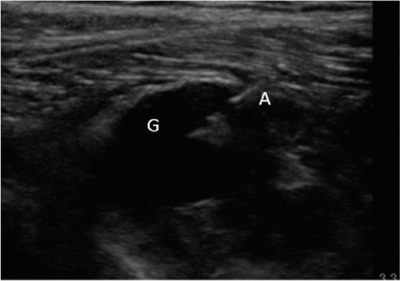

Ante estos hallazgos se decidió realizar ecografía clínica, objetivándose datos de neuropatía del nervio peroneo común (nervio engrosado, hipoecogénico y con pérdida del patrón fibrilar previo a su entrada en el túnel osteofibroso peroneo) coincidiendo con la compresión de una estructura compatible con un ganglión originado en la articulación tibio-peronea proximal. En ecografía dinámica, ante maniobras de flexo-extensión de pie, se objetivó un ascenso del ganglión y un mayor contacto con el nervio peroneo (Figura 1) a nivel de la zona de afectación neural. El paciente presentaba además un claro tinel ecográfico positivo a la compresión nerviosa y dolor a la ecopalpación del ganglión.

Fig. 1. Ecografía de corte axial del nervio peroneo común con características de neuropatía por compresión de ganglión. P: peroné. G: ganglión, resaltado perímetro para mejor visualización. NP: nervio peroneo común, que se encuentra engrosado, hipoecogénico y con pérdida del patrón fibrilar.